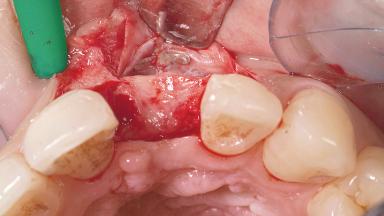

A 30-year-old female patient had lost tooth 21 and was referred to our clinic for consultation and treatment. Due to advanced apical infection, tooth 21 had been extracted two months earlier at another clinic and an acrylic-resin tooth had been bonded to the adjacent teeth. The patient desired implant treatment to avoid any damage to the adjacent natural teeth. While the patient had no history of any systemic disorder, she was a heavy smoker and exhibited medium to advanced periodontitis in the entire jaw. After the initial treatment to achieve a pocket probing depth of less than 4 mm and no bleeding on probing, a decrease in the height of the papillae mesial and distal to the extraction site and overall gingival recession were observed.

Bone Augmentation Horizontal|Staged

Augmentation Materials Autogenous chips|Membrane

Soft Tissue Grafting Simultaneous

Bone Volume Deficient horizontally, requiring prior grafting

Periodontal Status History of periodontitis or genetic predisposition

Soft Tissue Contour and Volume Slightly compromised